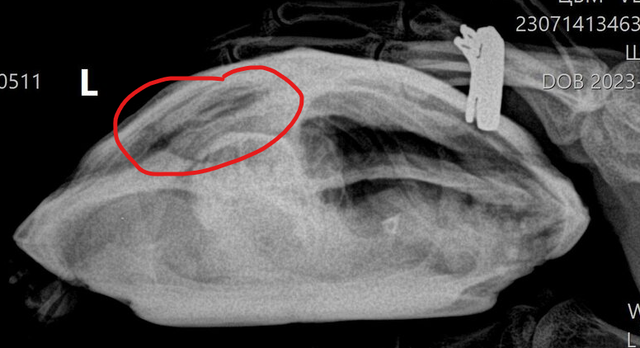

olga@ Ваше имя: Гоша Локация: Тульская область Опубликовано: 14 июля 2023 Автор Опубликовано: 14 июля 2023 (изменено) Рентген сделали в трёх проекциях, видимо мы не так поняли друг друга.Помогите пожалуйста, что нам дальше делать. Изменено 14 июля 2023 пользователем olga@

Консультанты moth Ваше имя: Мария Локация: Москва Опубликовано: 14 июля 2023 Консультанты Опубликовано: 14 июля 2023 @olga@ да, у неё проблемы с одним из лёгких. В норме на этой проекции оба лёгких выглядят как черная пустота (как в исходном примере №3), у Вашей одно лёгкое "мутное" - либо сдулось по какой-то причине, либо жидкость, пневмония и т.п. Здесь уже нужно врачу-герпетологу читать снимок и делать назначения, т.к. у консультантов нет для этого знаний. Это уже не форумный случай. По Туле у нас нет информации о хороших герпетологах, а наш врач, кто курирует форум, сейчас в отпуске на неделю (до понедельника). Могу Вам предложить либо написать её коллеге для онлайн консультации Ганькова Анастасия Сергеевна @Ansergan (ник в телеграмме) либо ещё онлайн консультирует Закружная Анжелика Дмитриевна https://t.me/anzhel_rept, но я не знаю какие у них цены за консультацию. Либо дождаться когда выйдет из отпуска наш врач, для форума у неё цена 300р за весь курс, оплата после консультации, но могут быть задержки в ответах сутки из-за высокой нагрузки. Черепаха сейчас продолжает нормально питаться?

Консультанты moth Ваше имя: Мария Локация: Москва Опубликовано: 22 июля 2023 Консультанты Опубликовано: 22 июля 2023 @olga@ здравствуйте! врач готова посмотреть тему и черепаху, актуально ещё? предварительно по моему описанию сказала, что может быть ателектаз легкого и это не лечится, так и будет жить с одним лёгким. Но я рентген ещё не скидывала, т.к. нужно для этого тему создавать.